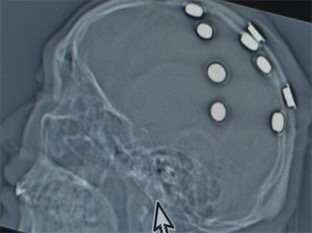

我苏网讯 近日,南京脑科医院接诊了一位年轻的癫痫患者,诊疗过程中,医生发现小伙头部有明显的异物感,再仔细一查,里面竟然藏着10块磁铁!这磁铁是从哪里来的,又怎么会跑进小伙的脑袋中呢?

接诊后,经过五个多小时的手术,医生将小伙头部10块铁磁片全部取出。记者量了量,发现每块磁铁直径约1厘米,厚度2毫米。那么,这些磁铁怎么会跑进何某的脑袋内呢?原来,5年前,何某通过网络广告得知,江苏一家诊疗机构可以通过"调节磁场"来控制癫痫发作。于是他专程前往,在头部植入了这十块"磁电极",结果癫痫发作反而更加频繁。